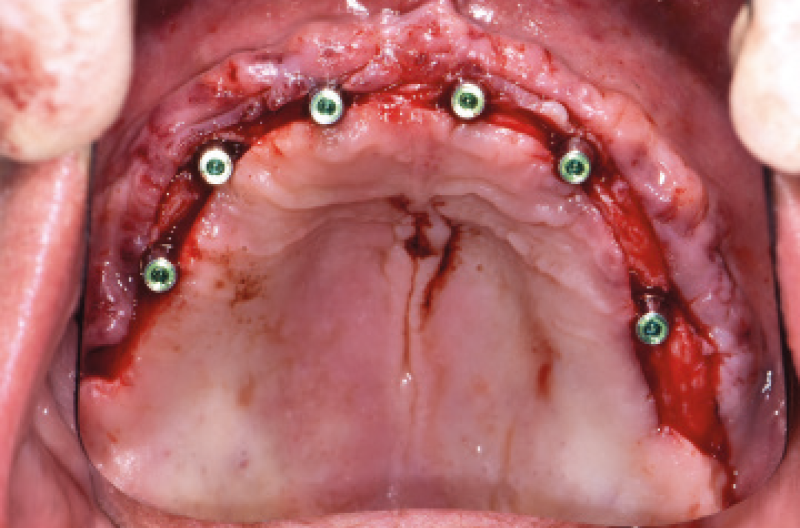

NellŌĆÖarcata inferiore ho posizionato distalmente 2 impianti Max Stability ├ś 3,75 mm L 12 e L 14 mm inclinati (ŌĆ£tiltatiŌĆØ) davanti ai forami mentonieri secondo il protocollo All-on-four, mentre nella zona sinfisaria ho inserito 2 impianti Narrow ├ś 2,9 L 12 mm (Figg. 15-20).

Fig. 15 – Guida replica protesica inferiore per la marcatura dei fori chirurgici

Fig. 16 – Esposizione del forame mentoniero di sinistra

Fig. 17 – Esposizione del forame mentoniero di destra

Fig. 18 – Inserimento degli impianti Narrow 2.9

Fig. 19 – Inserimento degli impianti distali tiltati

Fig. 20 – Vista dei 4 impianti inseriti nellŌĆÖinferiore

Utilizzando i monconi di prova, sono stati scelti i monconi MUA pi├╣ idonei e prelevati dalla valigetta All-on-Four/All-on-Six messa a disposizione dalla Leone: due MUA GH 1,5 mm angolati a 7,5┬░ e due MUA GH 3 mm angolati a 35┬░. Una volta posizionati negli impianti non mi restava che parallelizzarli, operazione resa facile dalla vite blu polifunzionale gi├Ā premontata e dalla possibilit├Ā di ruotare i monconi a 360┬░ (Figg. 21,22).

Fig. 21 – Visualizzazione dellŌĆÖinclinazione degli impianti

Fig. 22 – Posizionamento e parallelizzazione dei monconi MUA

Dopo aver inconato i monconi MUA definitivamente negli impianti con lŌĆÖapposito percussore con punta in PEEK, ho avvitato gli adattatori Conic sui MUA serrandoli con il cricchetto dinamomentrico protesico per trasformarli in monconi conometrici.

A questo punto ├© stato semplicissimo convertire la protesi mobile in una Toronto conometrica fissa provvisoria: dopo aver scaricato opportunamente la protesi in corrispondenza dei monconi MUA-Conic, ho applicato le cappette Fixed sui MUA-Conic attivandole con il percussore con punta in PEEK. Ho riempito le cavit├Ā con della resina da ribasatura intraorale e posizionato la protesi sopra le cappette Fixed in modo da inglobarle nella protesi. Dopo aver rimosso la protesi, ho lasciato allŌĆÖOdt. Pasquale Martino il compito di rifinirla. Infine la protesi ├© stata riposizionata in bocca e attivata con il percussore con punta in PEEK. LŌĆÖintero intervento si ├© concluso nellŌĆÖarco di 5 ore e il paziente ├© tornato a casa con la sua Toronto conometrica provvisoria inferiore e la protesi mobile superiore (Figg. 23-25).